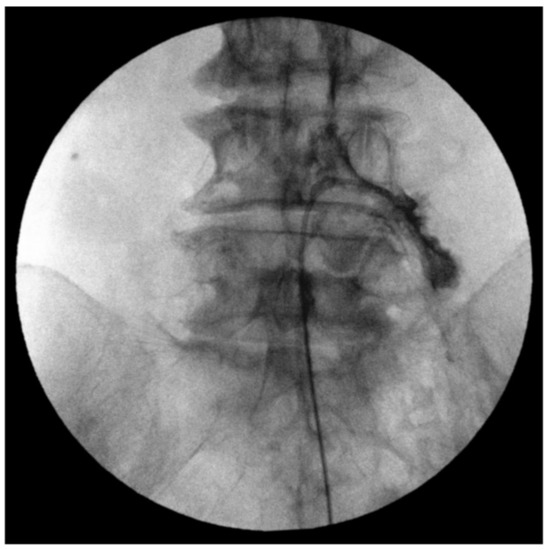

2.3. Fluoroscopy-Guided Lumbar Percutaneous Epidural Adhesiolysis